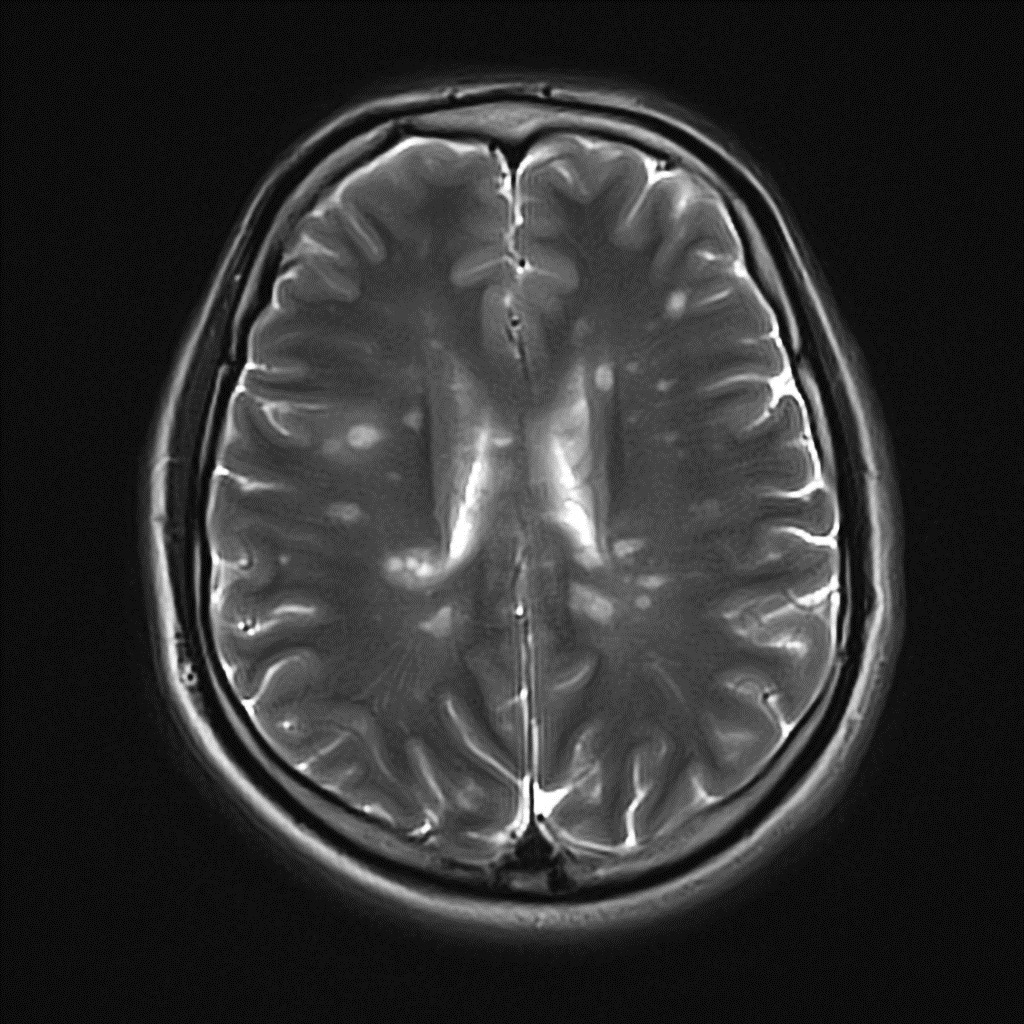

what are the typical imaging findings in MS?

periventricular white matter lesions seen on MRI (T2)

what are dawson fingers?

• radiological sign in MS

• seen on FLAIR images

• hyperintense lesions penpendicular to the corpus callosum